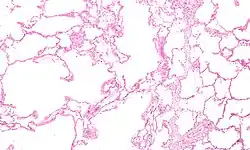

Micrograph of an emphysematous lung; emphysema is a respiratory disease, strongly associated with smoking. H&E stain.

Asthma, chronic bronchitis, bronchiectasis and chronic obstructive pulmonary disease (COPD) are all obstructive lung diseases characterised by airway obstruction. This limits the amount of air that is able to enter alveoli because of constriction of the bronchial tree, due to inflammation. Obstructive lung diseases are often identified because of symptoms and diagnosed with pulmonary function tests such as spirometry. Many obstructive lung diseases are managed by avoiding triggers (such as dust mites or smoking), with symptom control such as bronchodilators, and with suppression of inflammation (such as through corticosteroids) in severe cases. One common cause of COPD including emphysema, and chronic bronchitis, is tobacco smoking, and common causes of bronchiectasis include severe infections and cystic fibrosis. The definitive cause of asthma is not yet known.[4]